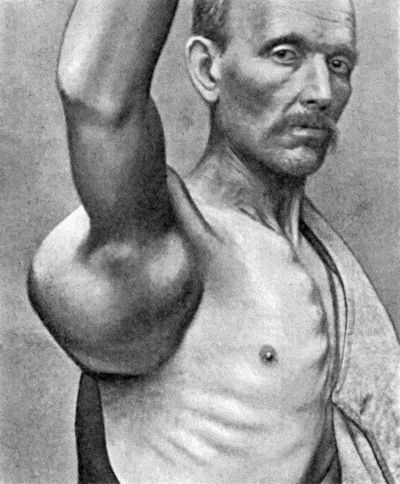

| 112. | Ossification in Muscles of Trunk in generalised Ossifying Myositis | 419 |

| 135. | Cadaver, illustrating the alterations in the Lower Limbs resulting from Ostitis Deformans | 475 |